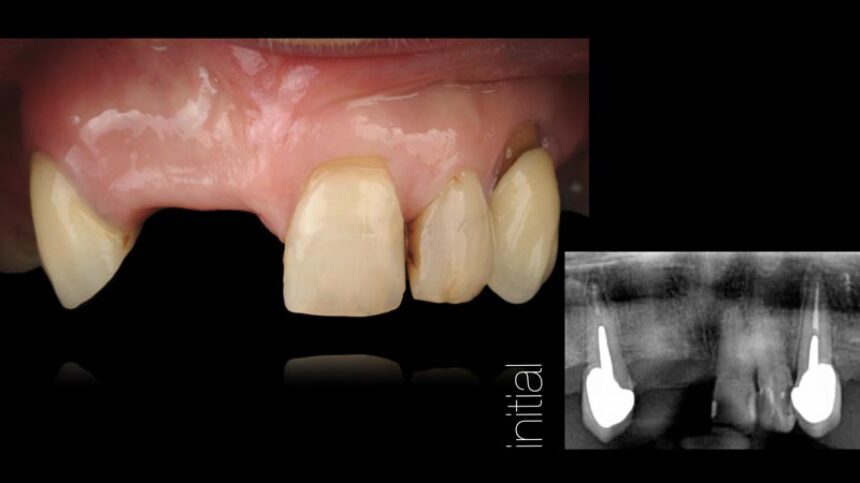

Αισθητική Οδοντιατρική με Εμφυτεύματα – βασικά επιστημονικά στοιχεία

Ανατομικοί παράγοντες με καθοριστικό ρόλο στην αισθητική αποκατάσταση επί εμφυτευμάτων – Διάγνωση και σχεδιασμός θεραπείας.

Διαχείριση μαλακών ιστών.

Χειρουργικές τεχνικές για την αύξηση των σκληρών και των μαλακών ιστών.